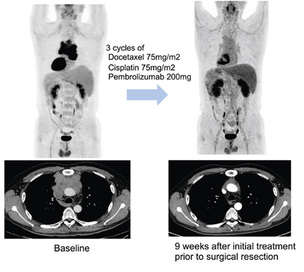

치료 옵션 제한적인 흉선암, 면역항암제 효과 ‘가능성’ 확인

치료 선택지가 많지 않은 흉선상피종양에서 면역항암제 기반 병용요법이 반응을 유도할 수 있다는 연구 결과가 제시됐다. 삼성서울병원 연구팀은 기존 항암화학요법에 면역항암제..